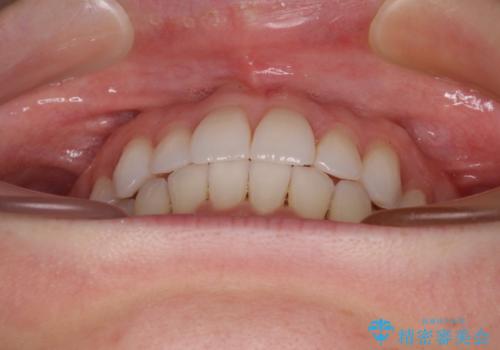

【モニター】インビザラインで気になるデコボコと八重歯をきれいに整える

- 上下前歯のデコボコ、特に右上の八重歯を気にして来院された患者様です。

妊娠、出産の予定があり、毎月の通院が困難となる可能性があったため、インビザラインによる矯正治療を行うこととしました。

事前に親知らずを抜歯しておき、出産時期に困ることのないように準備をした上で治療を開始しました。

治療後半では悪阻によりマウスピースの装着時間が不十分となることもありましたが、それよりも前にしっかりと装着時間を守って治療を進めることができたため、特に気になるところなく治療を終えることができました。